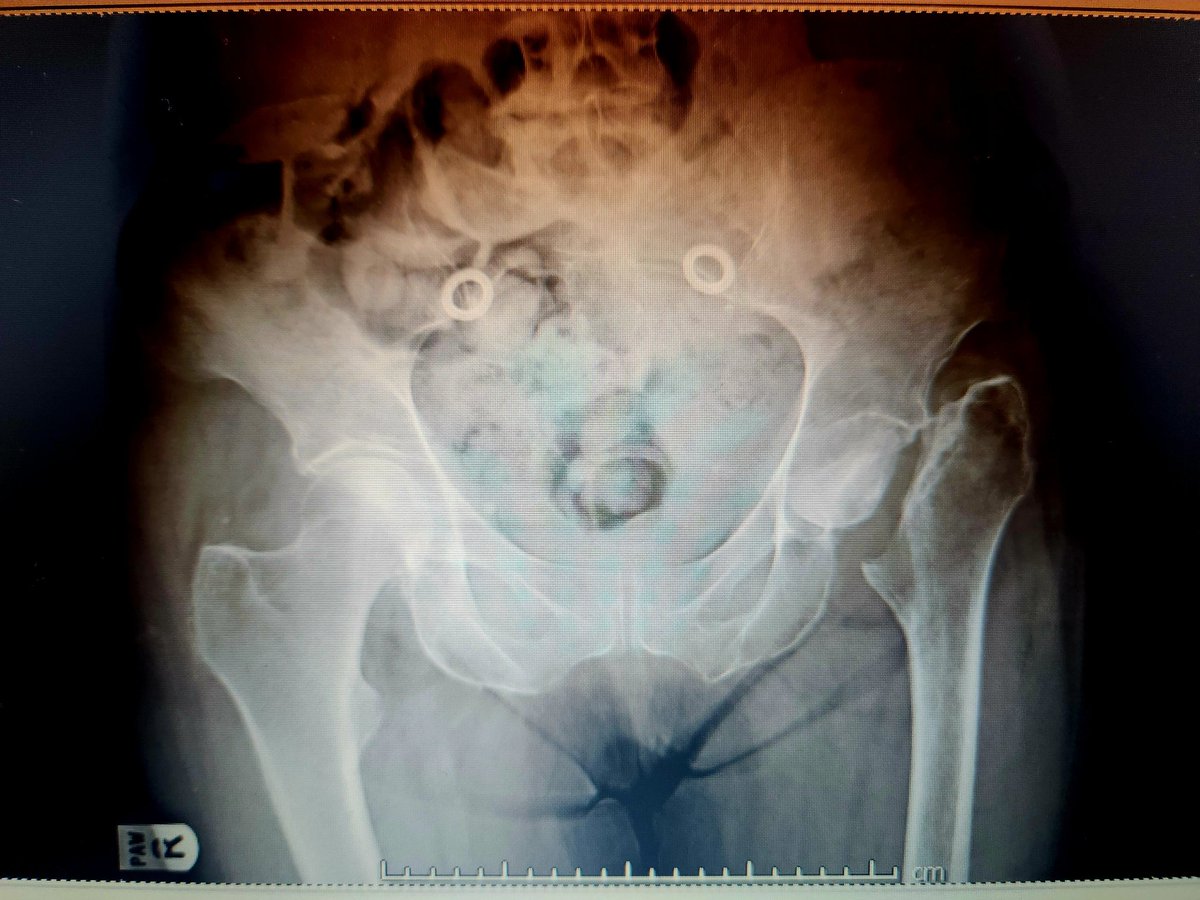

These are expensive too and a lot of hard work goes into getting pt on table. Thank you to YGC theatres & staff for the effort, @BetsiCadwaladr for support, fantastic MDT Wrightington, North Wales MDT, surgical experience @CavendishHip, my colleagues & Mr Kapur for dual operating